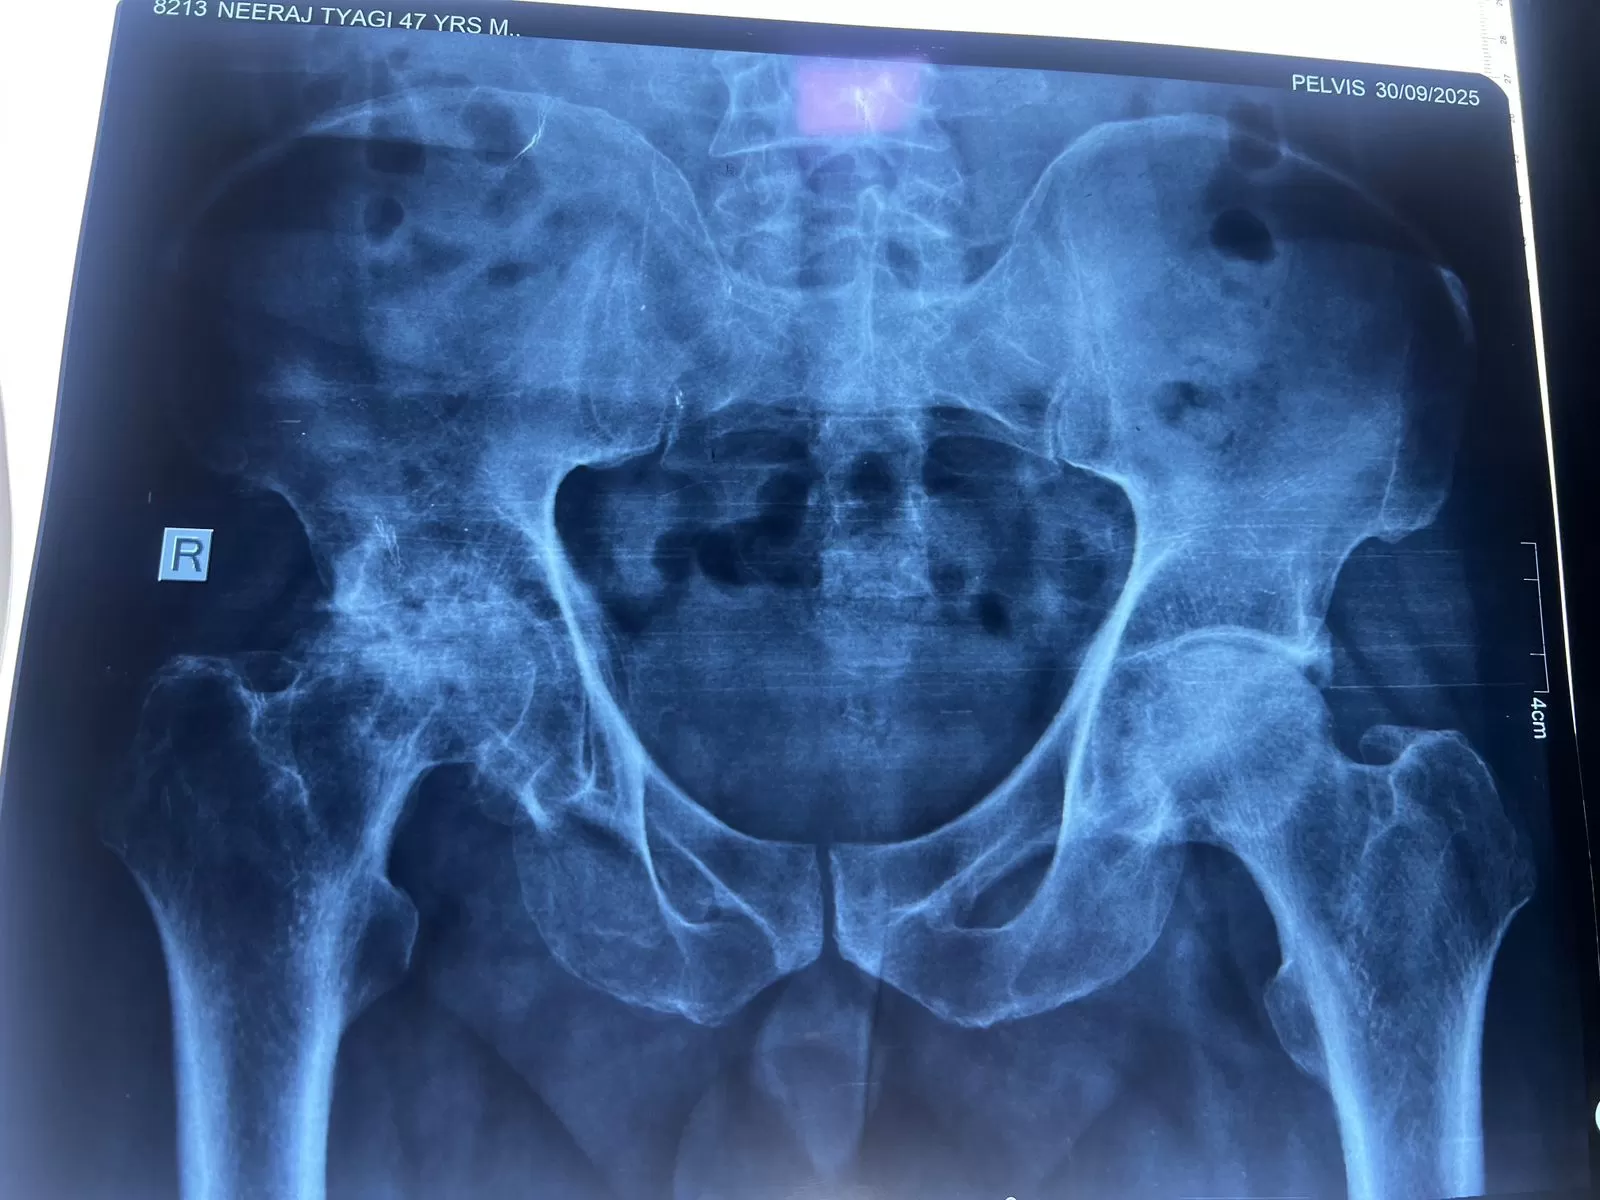

Mr. Neeraj Tyagi

Name: Mr. Neeraj Tyagi

Date of Operation: 30 September

Age: 48 Years